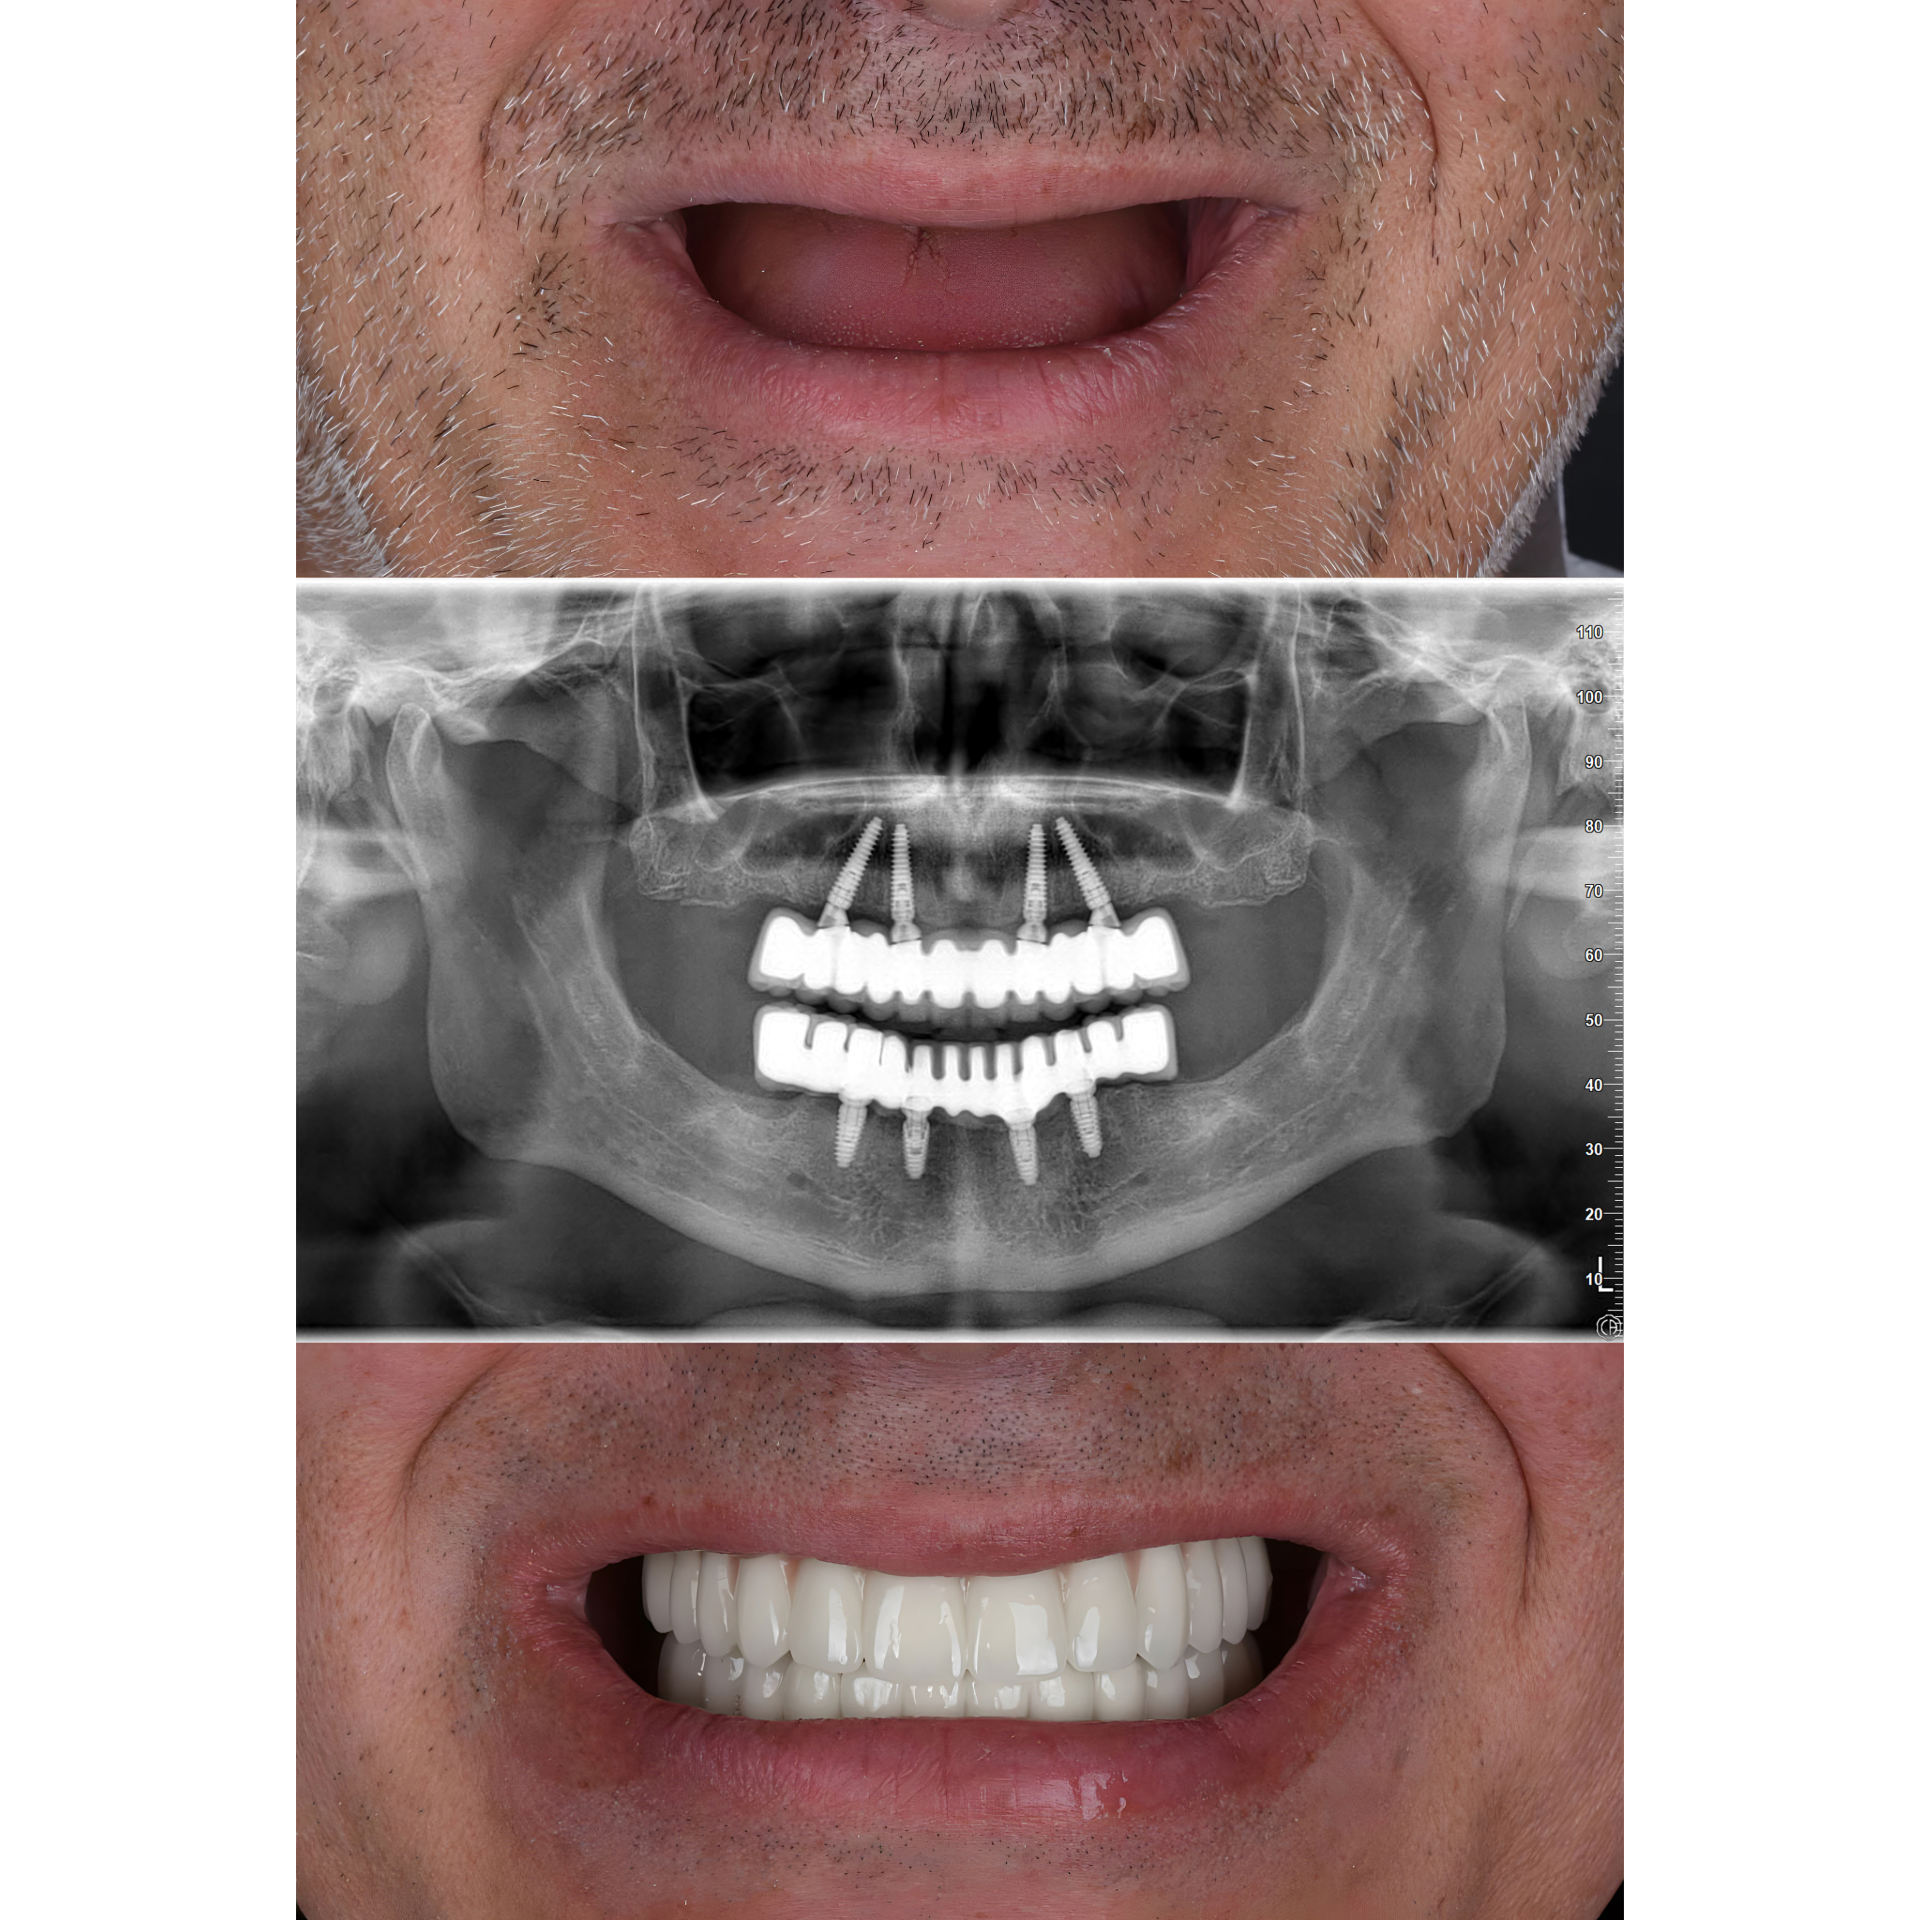

Prótese fixa total, parafusada sobre 4 a 6 implantes, usada para reabilitar uma arcada inteira em pacientes sem dentes (edêntulos).